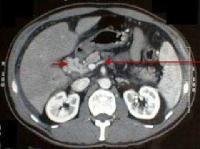

Foto 8: Tromboza de vena porta si transformare cavernoasa a venei porte la un pacient cu ciroza hepatica de etilogie alcoolica (sageata lunga indica vena splenica la jonctiunea cu vena mezenterica superioara, imediat inferior de tromboza, sageata scurta indica spre o forma serpigionoasa care indica transformarea cavernoasa a venei porte). |